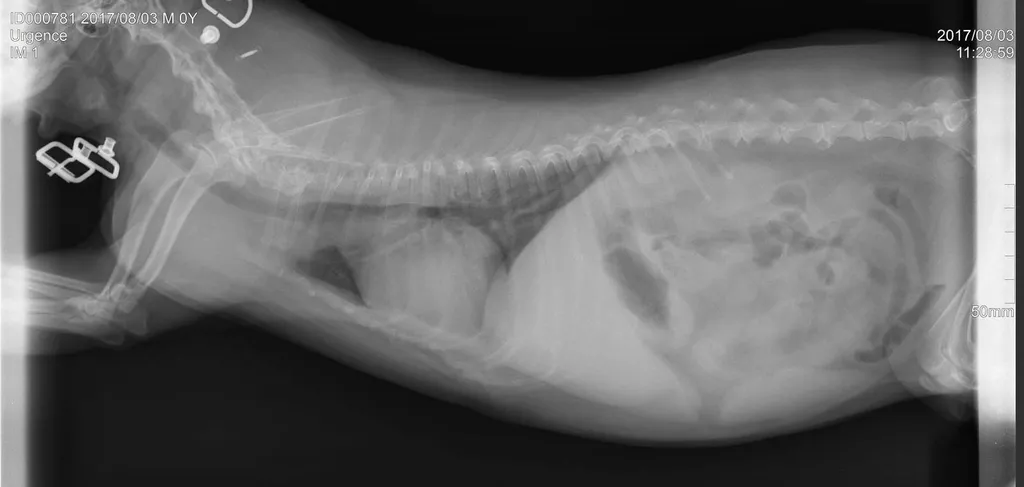

Une radiographie est un examen d’imagerie consistant à la prise de cliché au moyen d’un appareil à rayon X ceci afin de visualiser les différentes structures internes.

La radiographie reste indiquée dans de nombreuses affections, quelles soient respiratoires (radiographie cervicale ou thoracique), digestives (radiographie thoracique ou abdominale), locomotrices (membres, colonne), dentaires.

Votre chien, chat Nac est déposé sur la table de radiologie et différents clichés sont effectués dans différentes positions suivant la pathologie présentée.

Comme tout examen, il présente ses limites. Le principe de la radiographie étant l’utilisation du contraste (visualisation d’un tissu par rapport au tissu environnant et par rapport à sa radiodensité), certaines pathologies ne peuvent être que suspectées par radiographie mais nécessite d’autres examens (échographie, endoscopie, scanner, IRM).